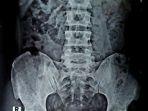

Ngilu, Mengaku Tak Sengaja Tertelan, Kabel Charger 60 Cm Ditemukan di Kantung Kemih Pria India Ini

Pasien pria berumur 30 tahun itu mulanya mengaku kepada Walliul, secara tak sengaja telah menelan kabel headphone sepanjang 60 cm.